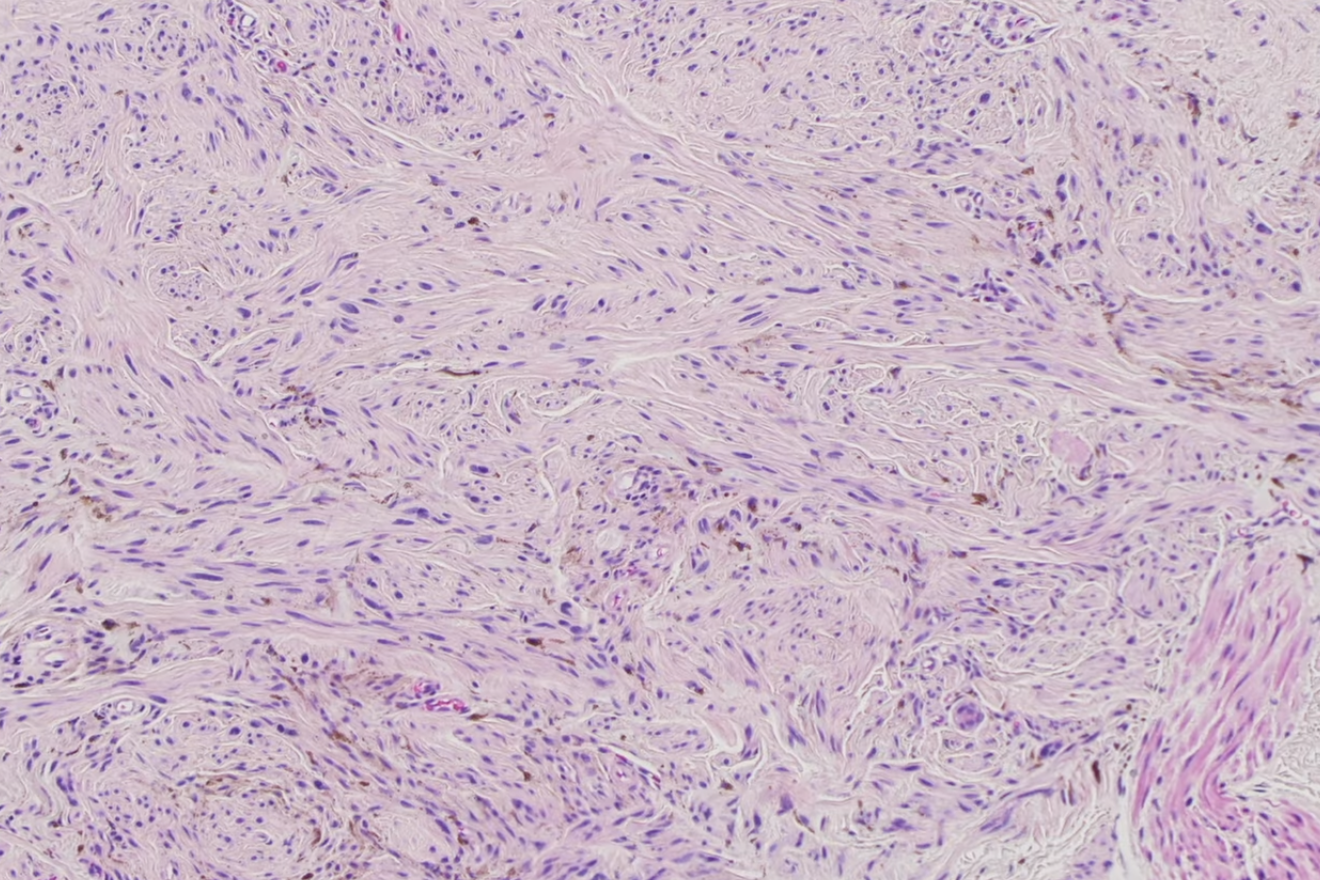

Histological features of DFSP

generally centered within the dermis or subcutis - **typically very bland. ** characterized by **spindle cells** with a **storiform to whorled pattern** Cytoplasm abundant and eosinophilic; **nuclei are monomorphic** and ovoid to elongated with variable mitotic activity Tumors infiltrate and expand fibrous septa; interdigitation among lobules of fat yields a **honeycomb pattern** Adnexal structures are spared Stroma may be collagenous, myxoid or microcystic